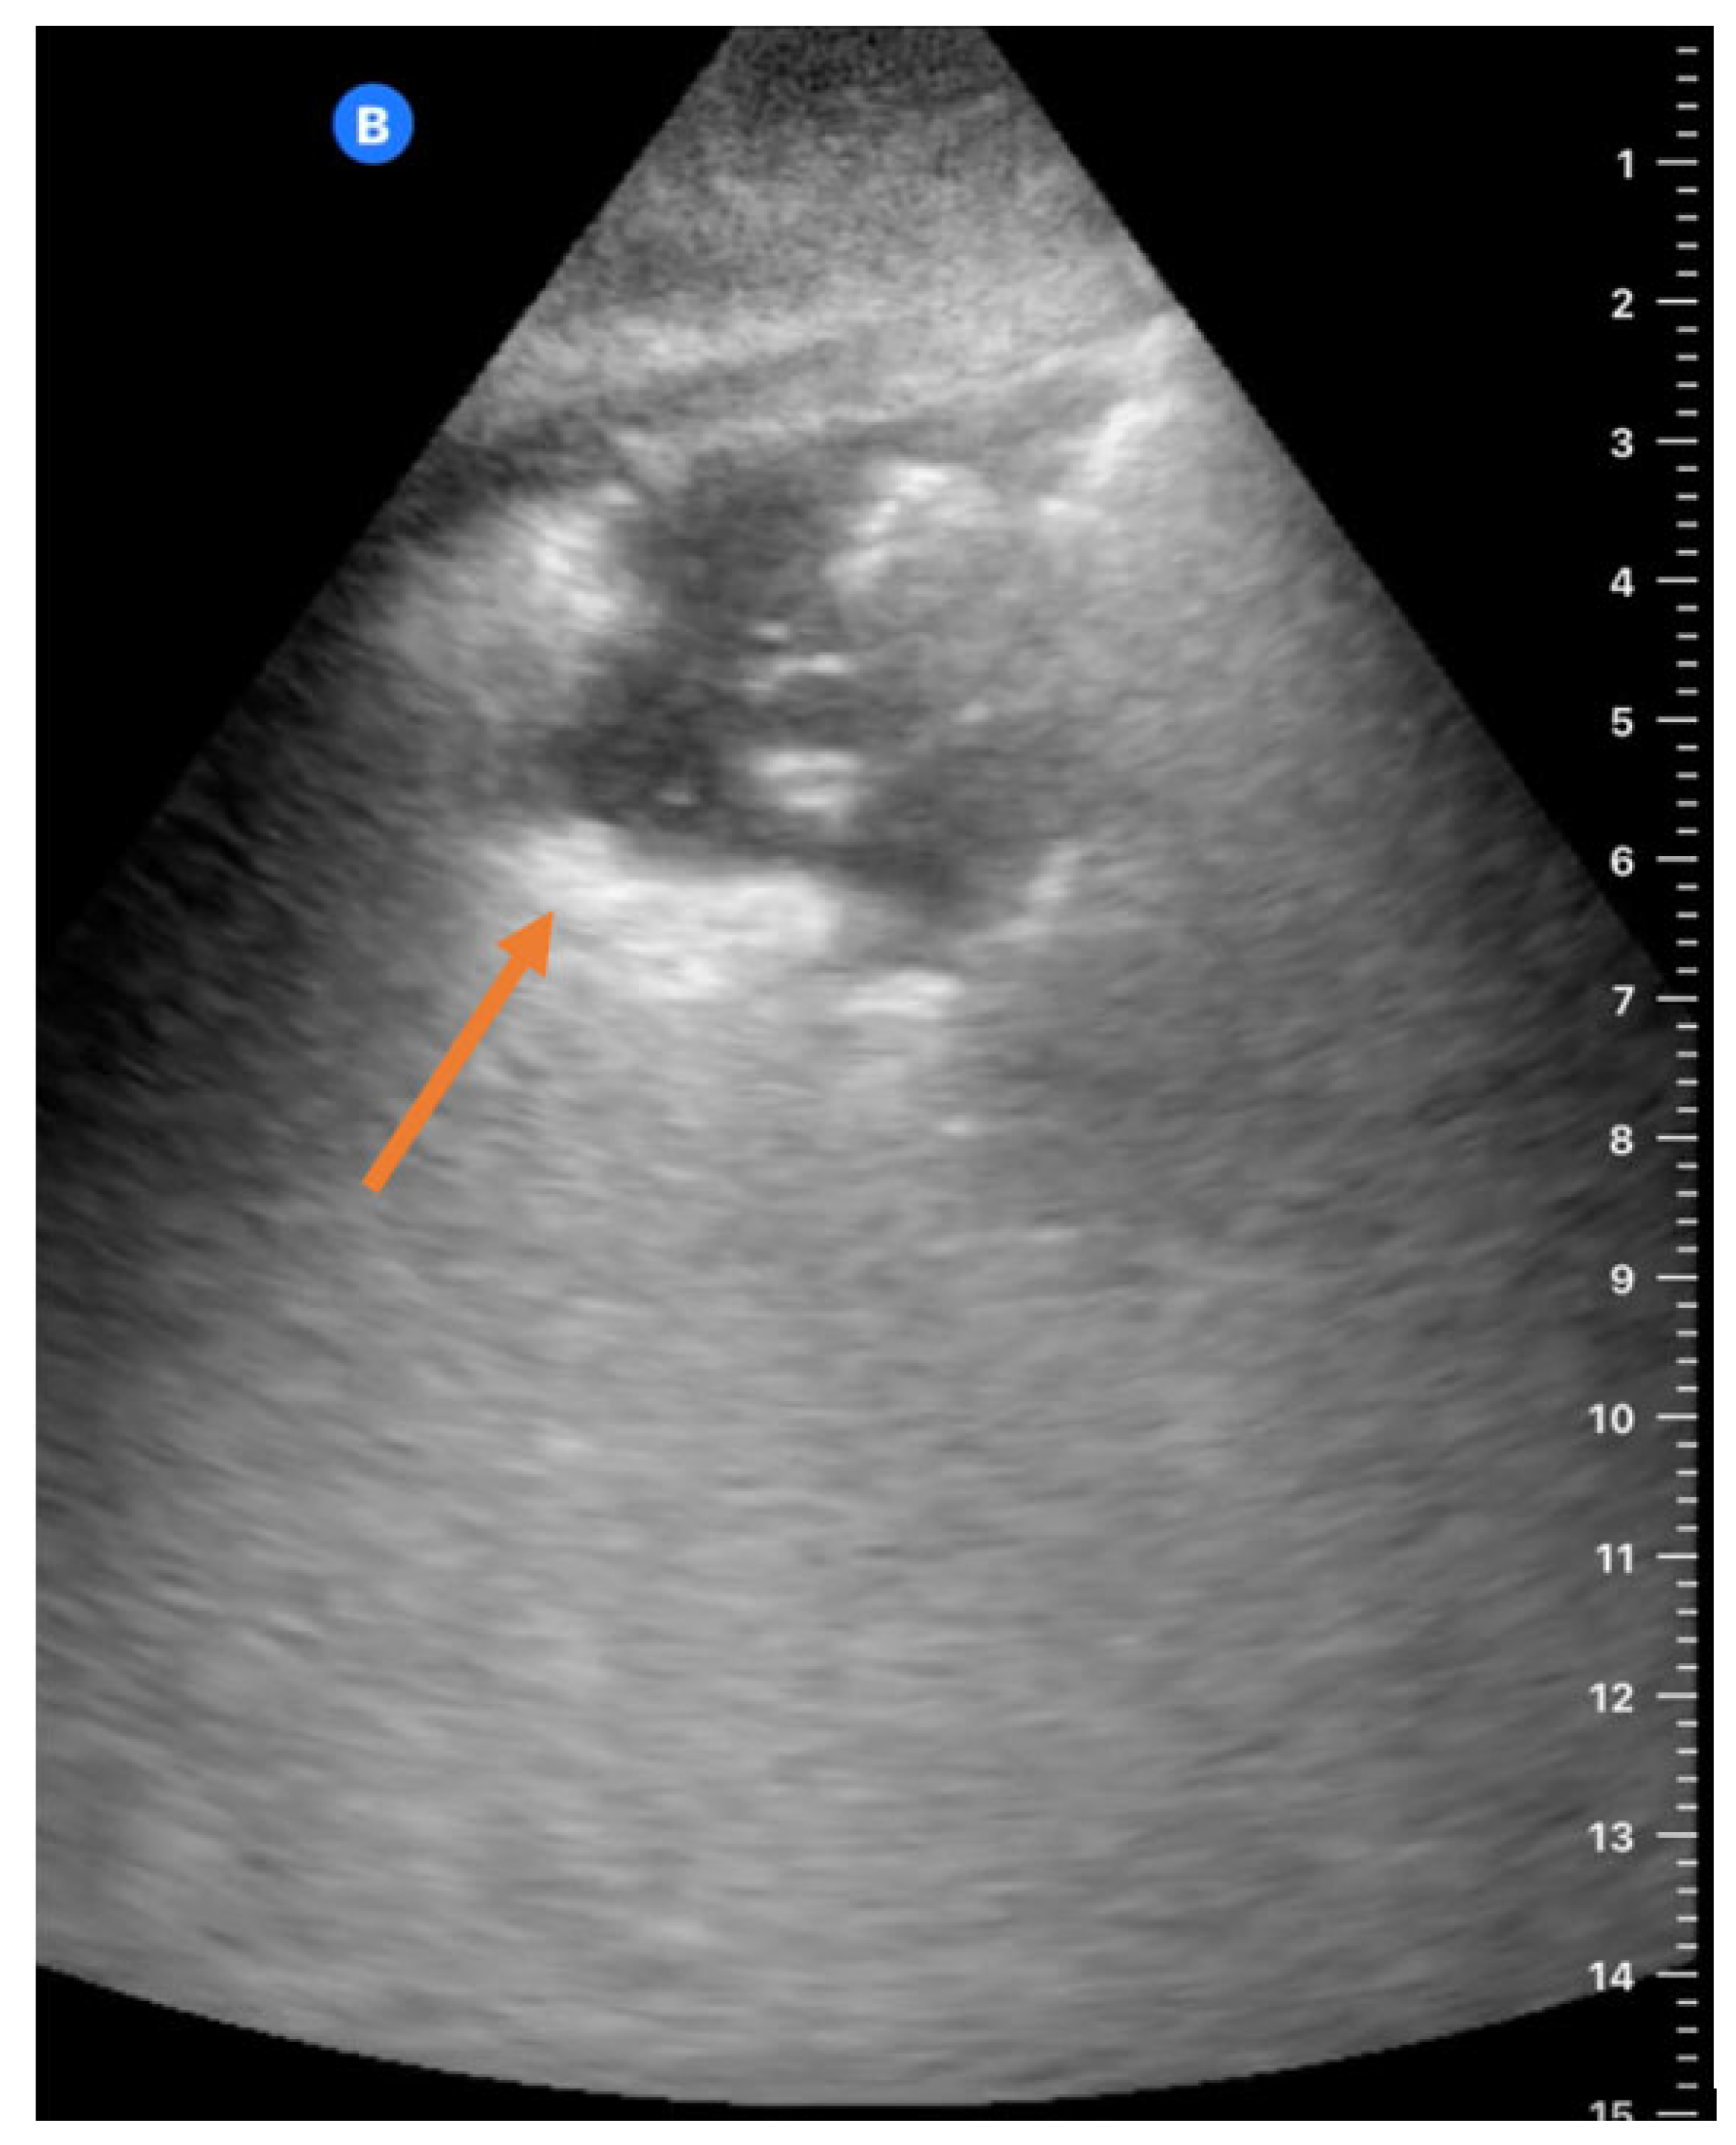

2.2. Focused Lung UltraSound